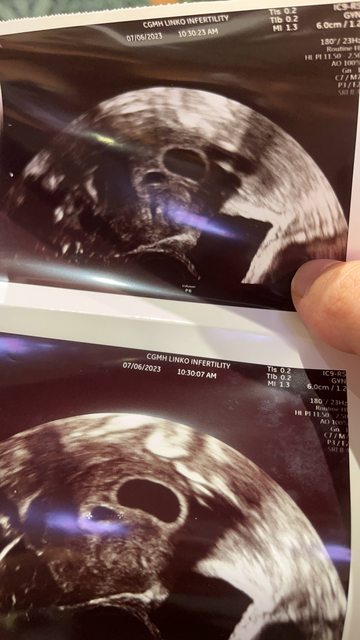

以下手機Po文請見諒。 跟太太(36歲)這次是凍胎6/19植入。 第一次檢查是在7/6,也就是第六週的時候,只有看到囊胚,裡面什麼都沒有。(如下圖) ,醫生當場說囊胚大小跟位置都算還可以,建議再等兩週。 https://i.imgur.com/TLJtMDC.jpg